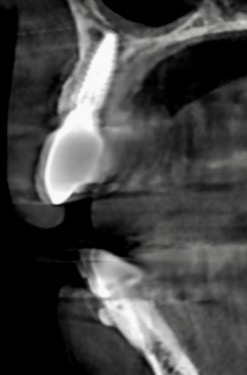

下記の症例は骨幅が薄く、このままでは長期的に安定したインプラント治療が不可能だったので、抜歯と同時に骨造成(GBR)を行い、その後歯肉移植(FGG)を行い、術後安定した経過を辿るよう配慮致しました。